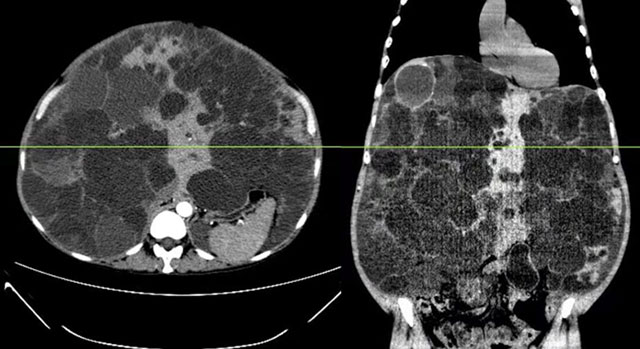

影像学可见巨大多囊肝占据腹腔

此例多囊肝患者,肝脏重量约为正常肝脏的11倍,进行肝移植手术非常复杂和困难。一是手术空间狭小、肝门显露困难;二是巨大病肝切除后有效循环容量丢失;三是术后巨大肝脏压迫的解除导致循环容量相对不足,还有血压波动及血流灌注不足引发的急性肾损伤等种种难题,要做好这个手术,必须“过关斩将”。

患者术前腹部 巨大多囊肝